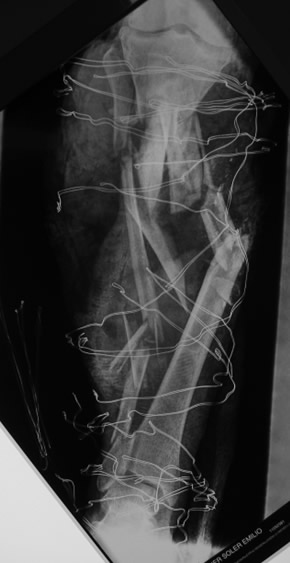

El paciente llegó de urgencias con un aplastamiento severo de la extremidad inferior con indicación de amputación en otro centro. La lesión era de alta energía con destrucción masiva de partes blandas y fractura hiperconminuta de tibia abierta. La urgencia del caso y la gravedad de las lesiones exigían una actuación inmediata y escalonada para intentar salvar la extremidad.

- Fractura hiperconminuta de tibia abierta con destrucción masiva de partes blandas

Paso 1: Limpieza quirúrgica y fijación provisional de esqueleto con fijación externa

Se limpió las heridas y se fijó provisionalmente el esqueleto con fijación externa en espera de delimitación de necrosis cutánea.